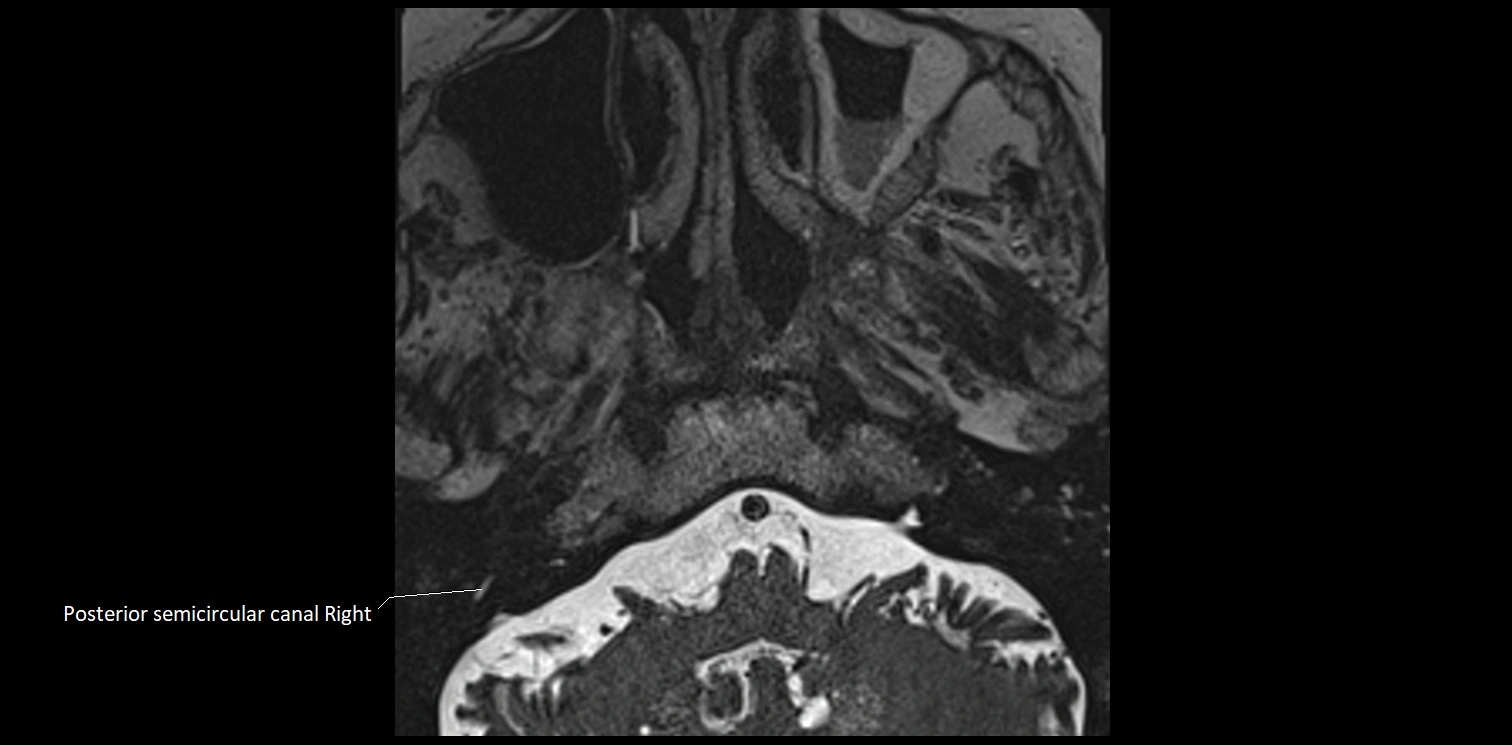

MRI Appearance

• The abducens nerve is a small, thin, linear structure

• Best visualized on high-resolution T2-weighted 3D MRI sequences (e.g., FIESTA or CISS)

• Seen as a hypointense (dark) line running from the brainstem at the pontomedullary junction, traversing the prepontine cistern, and entering Dorello’s canal under the petrosphenoidal ligament, then into the cavernous sinus, and finally the orbit

• May be challenging to visualize in standard MRI due to its small size

• Pathology may be inferred by absence, displacement, or enhancement of the nerve

MRI images

image